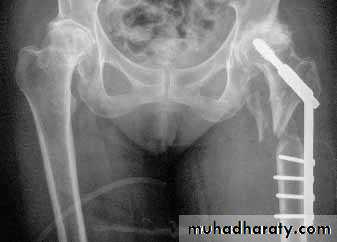

3.Treatment depend on the type and age of the patient

YOUNGER.

4.DHS.

ELDERLY PEOPLE

5.Austen Moore.6.Total hip replacement.

Same previous principle almost always treated by early internal fixation.(to overcome) the possible complications associated with prolonged recumbency.

To get the patient up and walking as soon as possible.

1.Sliding nail

2.L-plate

3.External fixation

Gamma nail